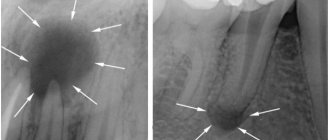

• X-ray diagnostics . Allows you to identify in detail even small defects on the root and determine the degree of caries damage. Most often, bite-wing radiographs and orthopantomograms are used for this.

Photo: caries inside a tooth root on an x-ray

It is difficult to independently diagnose root caries, and in some cases impossible. That is why you should not neglect a routine visit to the dentist, who can detect pathology at an early stage.

4. X-ray - a targeted photograph of one tooth or computed tomography. The presence and localization of obvious or hidden inflammation is determined with millimeter precision.